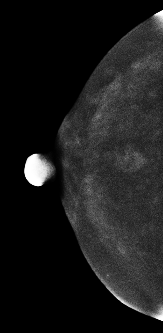

CESM图像:

常规检查:右乳偏外下象限见模糊类圆形结节影,CESM显示结节不均匀强化